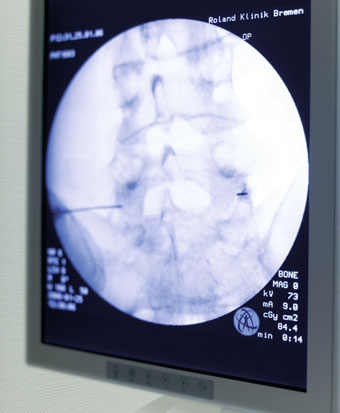

Die Wirbelsäule setzt sich aus einer großen Anzahl von Knochen und beweglichen Gelenken zusammen – und jedes einzelne Element kann Beschwerden hervorrufen. Für Sie als Patient ist es praktisch unmöglich, genau zu sagen oder zu zeigen, welches Gelenk oder Bewegungssegment Ihnen Schmerzen bereitet. Um der quälenden Ursache auf die Spur zu kommen, setzen wir unterschiedliche Diagnoseverfahren ein, beginnend mit der bildgebenden Diagnostik wie zum Beispiel Röntgen bis zur bildwandlergestützten Infiltration der Facettengelenke, Bandscheibe, des Rückenmarkkanals oder der Nervenwurzel.